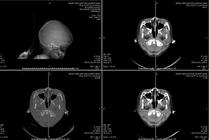

Hình ảnh vỡ xương sọ, tụ máu ngoài màng cứng đỉnh trái của bệnh nhi 3 tuổi - Ảnh BVCC

Kết quả chụp cắt lớp vi tính cho thấy hình ảnh vỡ xương sọ, chảy máu ngoài màng cứng đỉnh trái. Các bác sĩ chẩn đoán bệnh nhi bị chấn thương sọ não do ngã, vỡ xương, tụ máu ngoài màng cứng đỉnh trái.